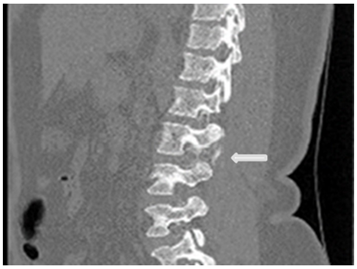

Under the suspicion of intracranial hypotensive headache caused by acute CSF leakage, a CT myelogram was performed Figure 3 the needle was set at L3/4 under radiographic control, contrast was repeatedly injected and x-ray images of lower and upper spine performed. After filling up to the cervical level of the epidural space, the patient’s whole spine was imaged with CT and extravasation was noted Figures 4 & 5.

Figure 3 white arrows pointing to contrast extravasation.